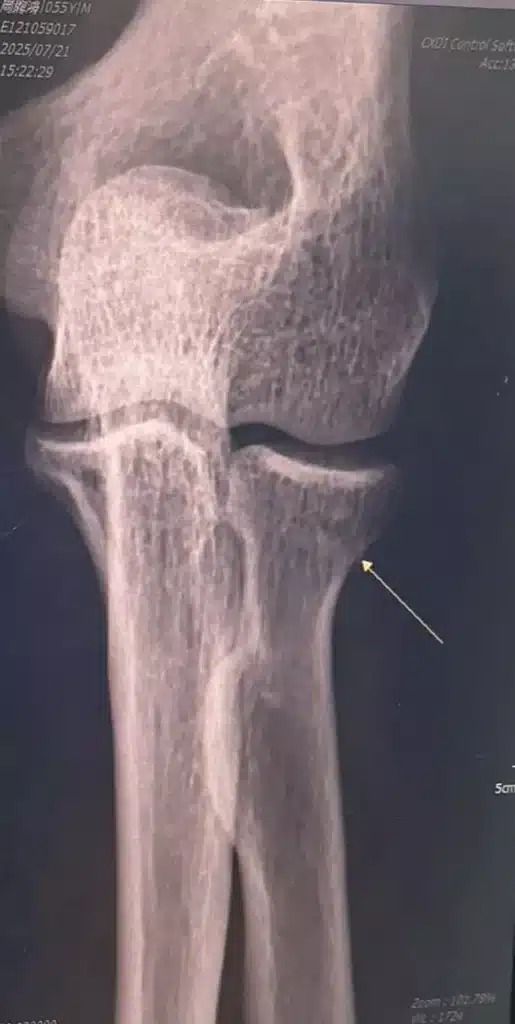

半夜到和平醫院急診,X光片證實:左手肘骨折。醫生冷靜地告訴我:「這樣至少要三個月才會好。」腦中浮現的卻是:再一個月,就是長宏二十週年慶與全球敏捷 CEO 大獎。我是主辦人,怎麼可能打著石膏上台?

幸運的是,命運也安排了貴人。隔週一,我遇到極有醫德的聯合醫院骨科醫師陳品全。他看完X光,第一句話就是:「這不嚴重,我幫你把石膏拆掉吧!」短短三天,我就從石膏的束縛中解脫。那一刻,我幾乎想大聲感謝上天。

醫師不選擇保守的「等三個月」,而是教我如何積極復健,並提醒要補充鈣片和高蛋白,加快骨頭癒合速度。甚至討論是否要進行快速復原手術 (自費8萬元),但最後決定靠復健與治療針來加速恢復。五週後,我真的能站上舞台,舉起沉重的獎座。醫師驚訝地說:「沒有人骨折五週能恢復到這種程度。」這大概就是專業、運氣與堅持交織的結果。